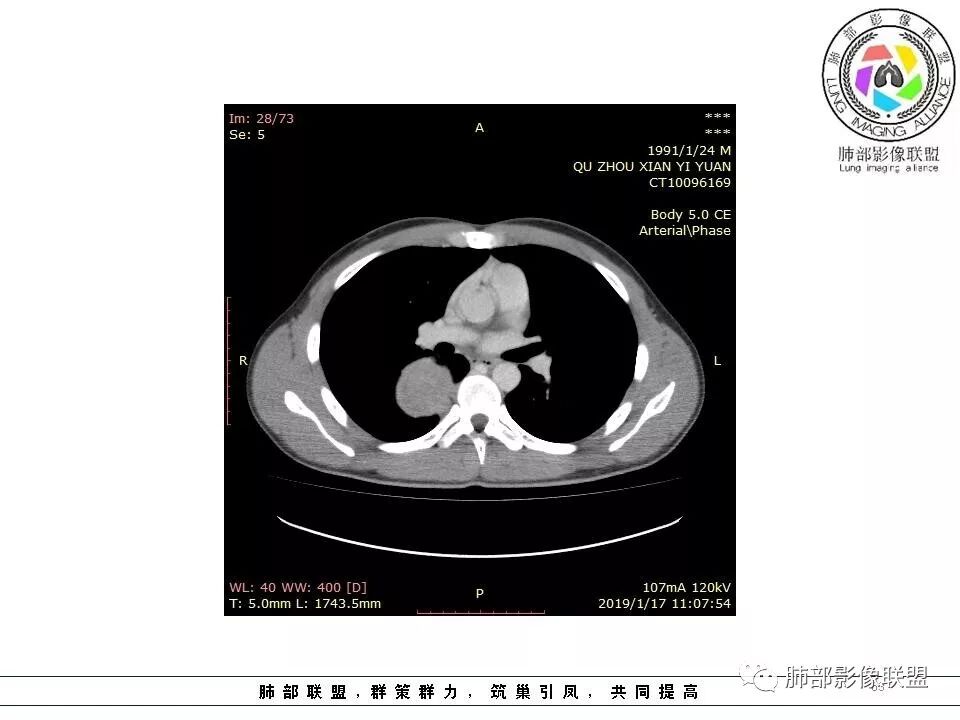

右后纵膈脊柱旁软组织占位,形态规则类圆,边缘光整,肺组织受压,胸膜尾,肋间动脉供血。中度不均匀延迟强化。

右后纵膈脊柱旁软组织占位,边界清晰,光整,肺组织受压。胸膜被掀起,肋间动脉供血,中度不均匀延迟强化。考虑神经鞘瘤,不除外纤维瘤

右后纵膈脊柱旁软组织影,与纵隔结构分界不清,形态规则类圆,边缘光整,肺组织受压,胸膜尾,肋间动脉供血。肺动脉推移,中度不均匀延迟强化。考虑神经来源,神经鞘瘤,神经纤维瘤二者不易鉴别。

青年男性,间断胸痛;右侧脊柱旁可见一类圆形软组织密度影,密度欠均匀,增强扫描呈轻中度持续强化,邻近肺组织及肺动脉推移,可见肋间动脉供血,部分胸膜下脂肪可见,部分层面似见与右侧椎间孔相连。考虑后纵隔神经源性肿瘤。

病灶定位脏层胸膜,肺组织受挤压,有胸膜尾征,动脉期可见血管支配,考虑肺动脉供血,静脉期,强化增强明显,符合快进慢出特点,病灶内可见低密度区,考虑胸膜孤立纤维瘤。

青年男性,间断胸痛。右后纵膈脊柱旁软组织占位,形态规则类圆,边缘光整,肺组织受压,D字征,胸膜尾,肋间动脉供血。中度不均匀延迟强化。无支气管进入考虑来源于肺外、肿块与脊柱间未见明显脂肪间隙,考虑来源于胸膜外,考虑神经源性肿瘤,建议穿刺活检。

青年男性,右侧脊柱旁软组织肿块,边缘膨隆,密度不均,临近肺组织受压、胸膜增厚,增强后动脉期呈不均匀强化,并可见肋间动脉供血,延迟期强化较均匀,定位肺外,首先考虑SFT,神经源性肿瘤待排

青年男性,右后上纵隔脊柱旁沟可见团状软组织影,边界清,密度尚均匀,推挤邻近肺组织,胸膜可见掀起,有肺动脉供血,增强轻度蛇皮样强化,纵隔淋巴结未见肿大,邻近骨质未见破坏,胸膜下脂肪间隙消失,考虑SFT孤立性纤维瘤可能性大,鉴别神经鞘瘤,节细胞瘤,建议活检。

青年男性,胸痛,右上纵膈脊柱旁肿块,形态光整规则,支气管被推移,临近的胸膜明显增厚,有胸膜掀起,增强后密度不均匀,可见蛇形血管征,血供似乎有两根血管供血,考虑SFT

右侧脊柱旁软组织肿块,胸膜尾征,肺动脉受压推挤,肺组织边缘清晰,增强,肿块由肋间动脉供血,延迟期强化不均匀,内见斑片状低密度区,定位肺外,后纵膈,神经源性肿瘤可能性大,鞘瘤?

青年男性,右侧脊柱旁占位,瘤肺界限清晰,支气管推移,胸膜尾,D字征,胸膜下脂肪影,蛇纹血管,双重供血,延迟强化,定位胸膜,支持sft

脏层胸膜主要由支气管动脉和肺动脉供血,壁层胸膜主要由支气管动脉,胸廓内动脉、肋间动脉供血

如果是肋间动脉,就不可能是脏层胸膜,可以是壁层或者纵膈

但是这个病人,肋间动脉供血吧,我倾向胸膜

肋间动脉供血,强化尚均匀,逐步强化

供血,体外供血,体循环,要么是壁层胸膜,要么胸膜外的,脏层胸膜应该是对内供血。病变里面的血管,除非是非常粗大迂曲的血管,不然,我不认为是其特点。

脏层胸膜肺内供血,壁层胸膜体外供血

这个病人不是肺动脉与支气管动脉供血,是肋间动脉供血

1.右上胸内脊柱旁类圆形肿块,质地似乎比较坚实,密度稍显不均,但未显示明确的坏死。

2.肋间动脉病供血也提示肿块来自后纵隔?